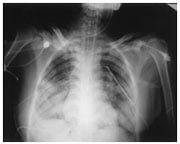

Photo courtesy of Chest, 1999 |

Chest radiography is necessary for anyone who is exposed to a blast. A characteristic "butterfly" pattern may be revealed upon x-ray. - Arterial blood gases, computerized tomography, and doppler technology may be used.

Photo Source: Reprinted by permission from Chest. X-ray Figure I in "Recovery from Blast Lung Injury: One year follow-up", by Hirshberg, Boaz, MD, et al. Dec 1999, Vol 116(6), p 1683-88.